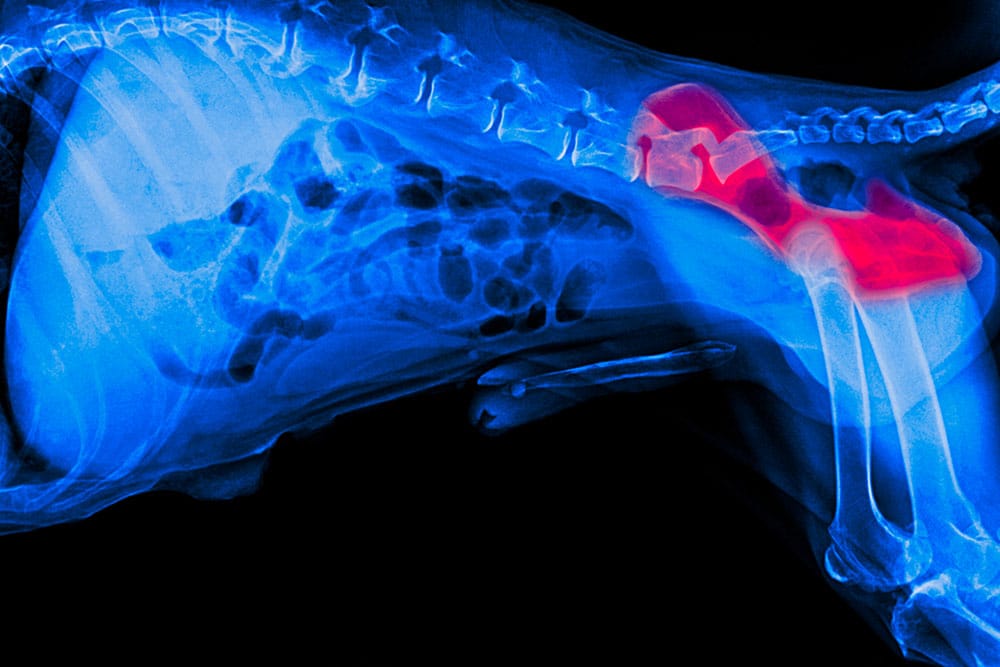

X-ray of a dog's hips and lower spine, with the left hip joint highlighted in red to indicate an area of concern or injury. The rest of the skeleton appears in blue.